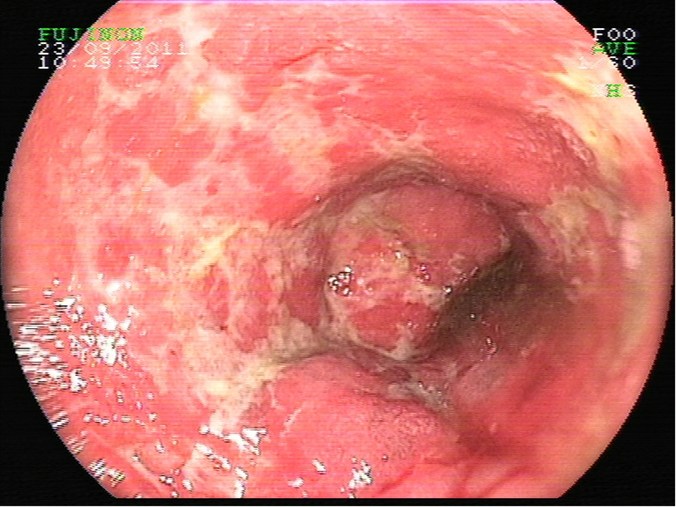

Escara post polipectomía

Escara post polipectomía, sutura con clips